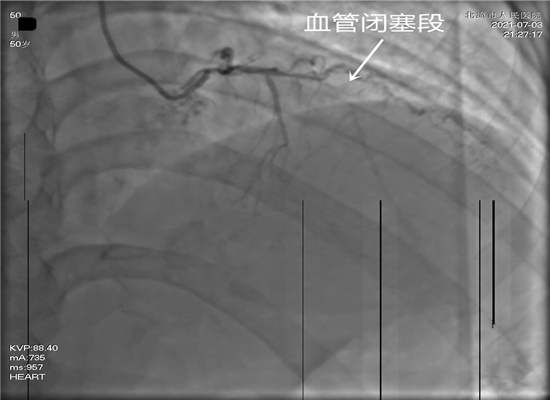

时间就是生命,这是一场与死神生死竞速的硬仗。21时15分,病人进入导管室,在赵子粼博士的主持下,张轩副主任亲自操刀,介入团队密切配合,快速穿刺桡动脉、置管、造影,升压,开通闭塞血管,植入支架。经过约50分钟的全力救治,成功挽救了患者的生命。目前,术后患者症状明显改善,恢复较好。

相关连接介绍:近年来,介入手术在我院已成功开展近1400例。据赵子粼博士介绍,急诊PCI手术,是指患者发生急性心肌梗死后12小时内进行的冠状动脉血运重建,患者首先在心脏导管室行冠状动脉造影术,找出冠状动脉病变血管及病变部位,对病变部位行经皮冠状动脉腔内成形术和植入支架,使闭塞的血管得以再通,梗死的相关心肌得以及早的再灌注和功能恢复。这是一项恢复冠状动脉血流最直接、最有效的治疗法之一,具有冠状动脉通畅迅速,残余狭窄轻和近、远期预后佳等优点,对减少心肌梗死的并发症,提高存活率、降低病死率和致残率都有重要意义。